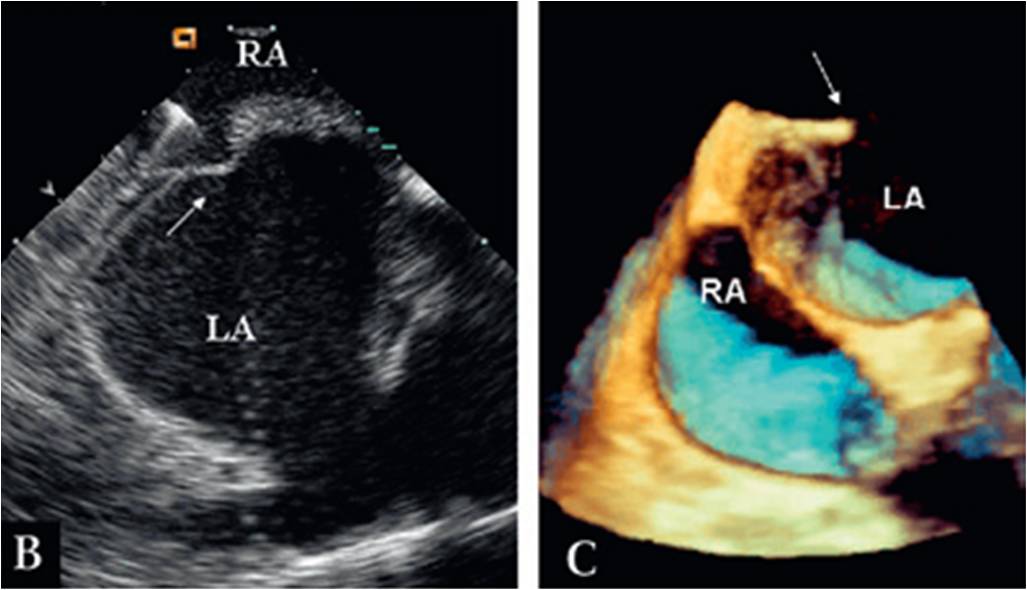

One caution : A common mistake done is eustachian valves is taken as false IVC rim and the device is implanted and later facing issuers. So, a meticulous TEE imaging is neccessary .